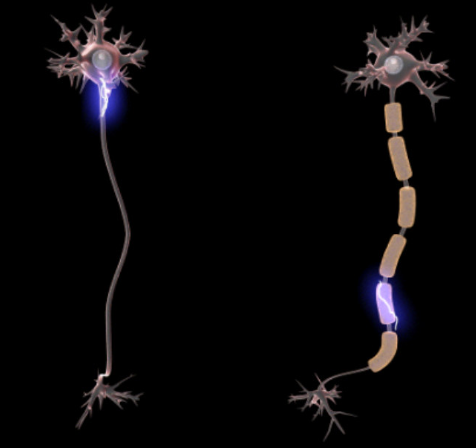

루게릭병의 초기 단계에서는 신체 능력이 점진적으로 그리고 대수롭지 않게 저하되는 것을 느낄 수 있습니다. 이러한 초기 징후는 흔히 간과되거나 대수롭지 않게 여기는 경우가 많지만, 루게릭병의 더 뚜렷한 증상의 전조로 작용합니다.

루게릭병의 초기 징후 중 하나는 근육에 침투하여 근육의 기능과 손재주나 손을 움직이는 신경들을 손상시키며 미묘하게 환자의 근육기능들을 약화시킨다고 합니다.

특히 복잡한 동작을 실행하거나 단추를 잠그거나 펜을 정교하게 휘두르는 등 정밀한 운동 제어가 필요한 물체를 조작하는 데 약간의 어려움이 생길 수도 있습니다. 이렇게 약간 누치채기 어렵게 조금씩 조금씩 영향을 받은 근육에 스며들어 앞으로 계솏해서 몸을 잠식해나가는 무서운 질환입니다.

이렇게 점진적으로 약화됨과 함께 피부에서는 근육 경련, 즉 근경련현상 나타나며 해당증세가 동반됩니다.

정말 발병하기 이전에는 쉽게 눈에 띄지 않는 이 떨림은 신체 내부에 근본적인 증세들이 일어나고 악화되고 있음을 나타냅니다. 이러한 증상만으로는 루게릭병이 확실하지는 않지만, 다른 증상과 함께 나타나면 미묘한 위험 신호로 작용하여 추가 조사가 필요할 수 있습니다.